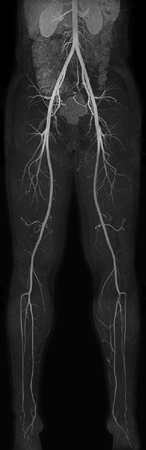

Non-subtraction MR Angiography

Utrecht Medical Center, The Netherlands

Used Solution

• System

• Coil

• Clinical Application